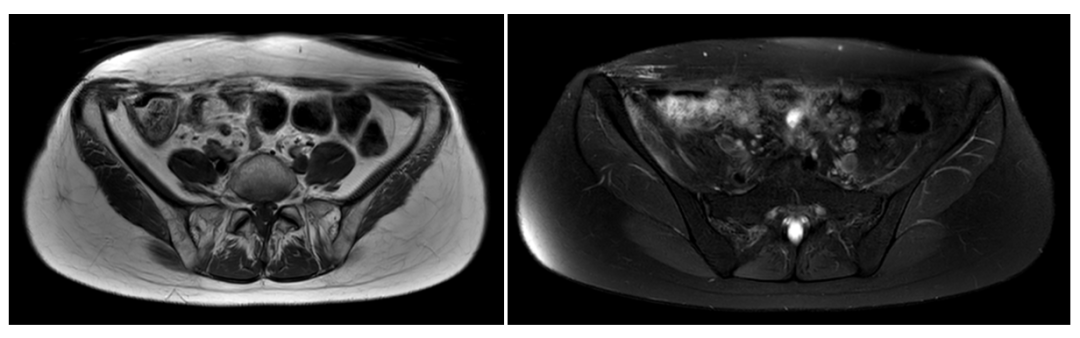

术前影像

术后6个月

术后12个月

术后18个月